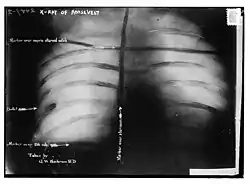

Posteriormente, sondagens e radiografias mostraram que a bala havia se alojado no músculo peitoral de Roosevelt, mas não penetrou na pleura. Como os médicos concluíram que seria menos perigoso deixá-lo no lugar do que tentar removê-lo (Roosevelt tornou-se presidente após o assassinato do próprio McKinley, onde o ferimento à bala gangrenou), Roosevelt carregou a bala consigo pelo resto da vida. Tanto o presidente William Howard Taft, quanto o candidato democrata Woodrow Wilson suspenderam sua própria campanha até que Roosevelt se recuperasse e retomasse a sua. Quando questionado se o tiroteio afetaria sua campanha eleitoral, ele disse ao repórter: "Estou em forma como um alce". O alce tornou-se um símbolo de Roosevelt e do Partido Progressista; muitas vezes era referido simplesmente como Partido Bull Moose. Ele passou duas semanas se recuperando antes de retornar à campanha. Mais tarde, ele escreveu a um amigo sobre a bala dentro dele: "Não me importo mais com isso do que se estivesse no bolso do meu colete."

Posteriormente, sondagens e radiografias mostraram que a bala havia se alojado no músculo peitoral de Roosevelt, mas não penetrou na pleura. Os médicos concluíram que seria menos perigoso deixá-lo no lugar do que tentar removê-lo, provavelmente lembrando o que havia acontecido com o antecessor imediato de Roosevelt, que morreu depois que o ferimento da bala infeccionou, e Roosevelt carregou a bala consigo pelo resto de sua vida.[16][17] Anos mais tarde, quando questionado sobre a bala dentro dele, Roosevelt diria: "Não me importo mais com isso do que se estivesse no bolso do meu colete."[18]